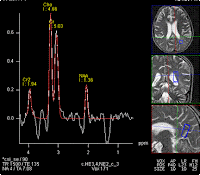

MR spectroscopy from left parieto-occipital white matter, which has the maximum hyperintensity, shows, as expected raised choline, decreased NAA and presence of lactate, i.e changes of demyelination and tissue loss

MRS from right parieto-occipital white matter also shows decreased NAA/Cho ratio and raised lactate

However, noteworthy is the presence of similar changes on spectroscopy in the normal appearing areas too